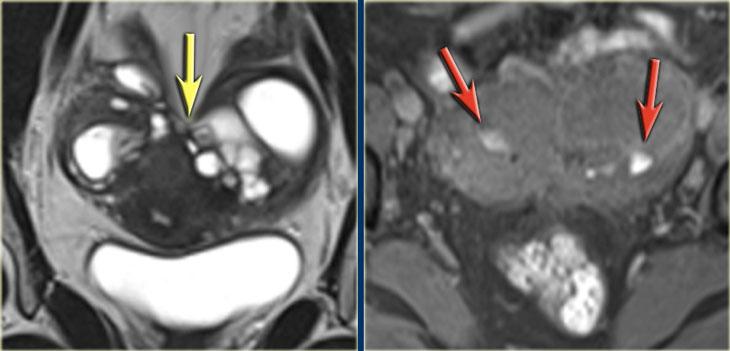

TRÁI: T2W mặt phẳng trán: buồng trứng áp sát nhau do dính. PHẢI: T1W+FS mặt phẳng trán minh họa các ổ xuất huyết nhỏ (mũi tên đỏ)

Hình ảnh T2W và T1W kỹ thuật ức chế mỡ bên trái cho thấy bệnh nhân lạc nội mạc tử cung có hai buồng trứng áp sát nhau (‘buồng trứng hôn nhau’), là kết quả của sự hình thành dính lan rộng.

Ở bệnh nhân này, một nang xuất huyết nhỏ của buồng trứng trái và một mảng nông xuất huyết cũng được ghi nhận (tăng tín hiệu trên T1, mũi tên đỏ).

Nang lạc nội mạc tử cung (mũi tên vàng), ứ dịch vòi trứng (mũi tên đỏ) và u xơ cơ tử cung (mũi tên xanh lam).

Các hình ảnh này thuộc về một bệnh nhân có nang lạc nội mạc tử cung ở buồng trứng phải (mũi tên vàng).

Tổn thương biểu hiện tín hiệu trung gian trên T2 và tăng tín hiệu trên chuỗi xung T1 xóa mỡ.

Ngoài ra còn có:

- Ứ dịch vòi trứng với tăng tín hiệu trên chuỗi xung T2W và giảm tín hiệu trên chuỗi xung T1 xóa mỡ (mũi tên đỏ).

- U xơ cơ tử cung với giảm tín hiệu trên chuỗi xung T2W và tín hiệu trung gian trên chuỗi xung T1 xóa mỡ (mũi tên xanh lam).